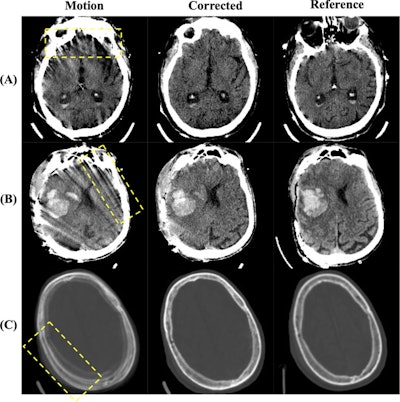

Visual examples of image quality improvements. (A) and (B) show corrections of motion artifacts within the brain tissue, where (A) corrects the star-like artifacts originating from the skull and (B) corrects the severe streaking artifacts across the brain. (C) shows the removal of a 'double skull' artifact caused by substantial head motion. Image display window is [0,80]HU for (A) and (B) and [−500, 1500]HU for (C). Images and caption courtesy of Academic Radiology.Visual examples of image quality improvements. (A) and (B) show corrections of motion artifacts within the brain tissue, where (A) corrects the star-like artifacts originating from the skull and (B) corrects the severe streaking artifacts across the brain. (C) shows the removal of a "double skull" artifact caused by substantial head motion. Image display window is [0,80]HU for (A) and (B) and [−500, 1500]HU for (C). Images and caption courtesy of Academic Radiology.

The investigators applied a pretrained diffusion model to correct motion artifacts in the portable scans; each of the 67 cases yielded three volumes: original (motion group), corrected (corrected group), and fixed (reference group). Three readers -- one neuroradiologist, one neuroradiology fellow, and one radiology resident -- reviewed the images in random order and scored eight lesion types and four image quality metrics on a 5-point Likert scale.